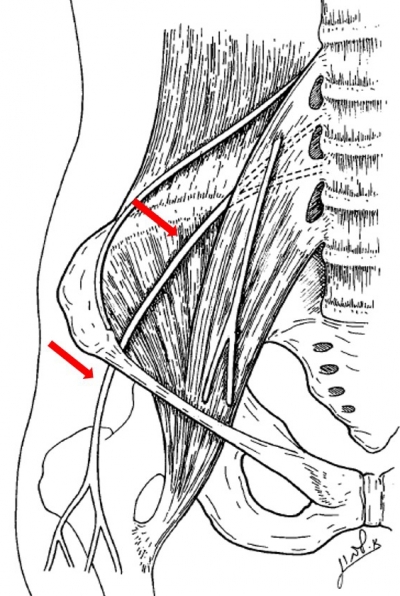

股外侧皮神经出骨盆时与髂前上棘的关系

有学者将股外侧皮神经穿出点的解剖变异进行归纳,将其分为以下四型:

A型:髂前上棘后2cm以远通过髂嵴(2.5%);

B型:髂前上棘后2 cm内通过髂嵴(10.0%);

C型:经髂前上棘通过(32.5%);

D型:经髂前上棘前(内)侧、腹股沟韧带外1/3深面通过髂筋膜与腹股沟韧带(或韧带外侧端两层)之间的骨纤维管道出骨盆入股部(55.0%)。

从分型中我们可以看出,D型为大部分股外侧皮神经穿出点所在部位,因此髂前上棘前内侧局部为常见的股外侧皮神经穿出点。

股外侧皮神经为何会出现损伤,那还得先从神经的解剖走行说起。股外侧皮神经源自L2-3神经前支后股,它从腰大肌外缘向下经髂肌前跨过髂窝,近似直角转折进入髂前上棘内侧腹股沟韧带下的纤维性管道内。之后出纤维管道后行于大腿阔筋膜深部,于髂前上棘下方3.0~5.0 cm处穿出阔筋膜。而股外侧皮神经在纤维管道内和股部阔筋膜穿出点的神经干相对固定,容易受到牵张、挤压和摩擦后发生损害。